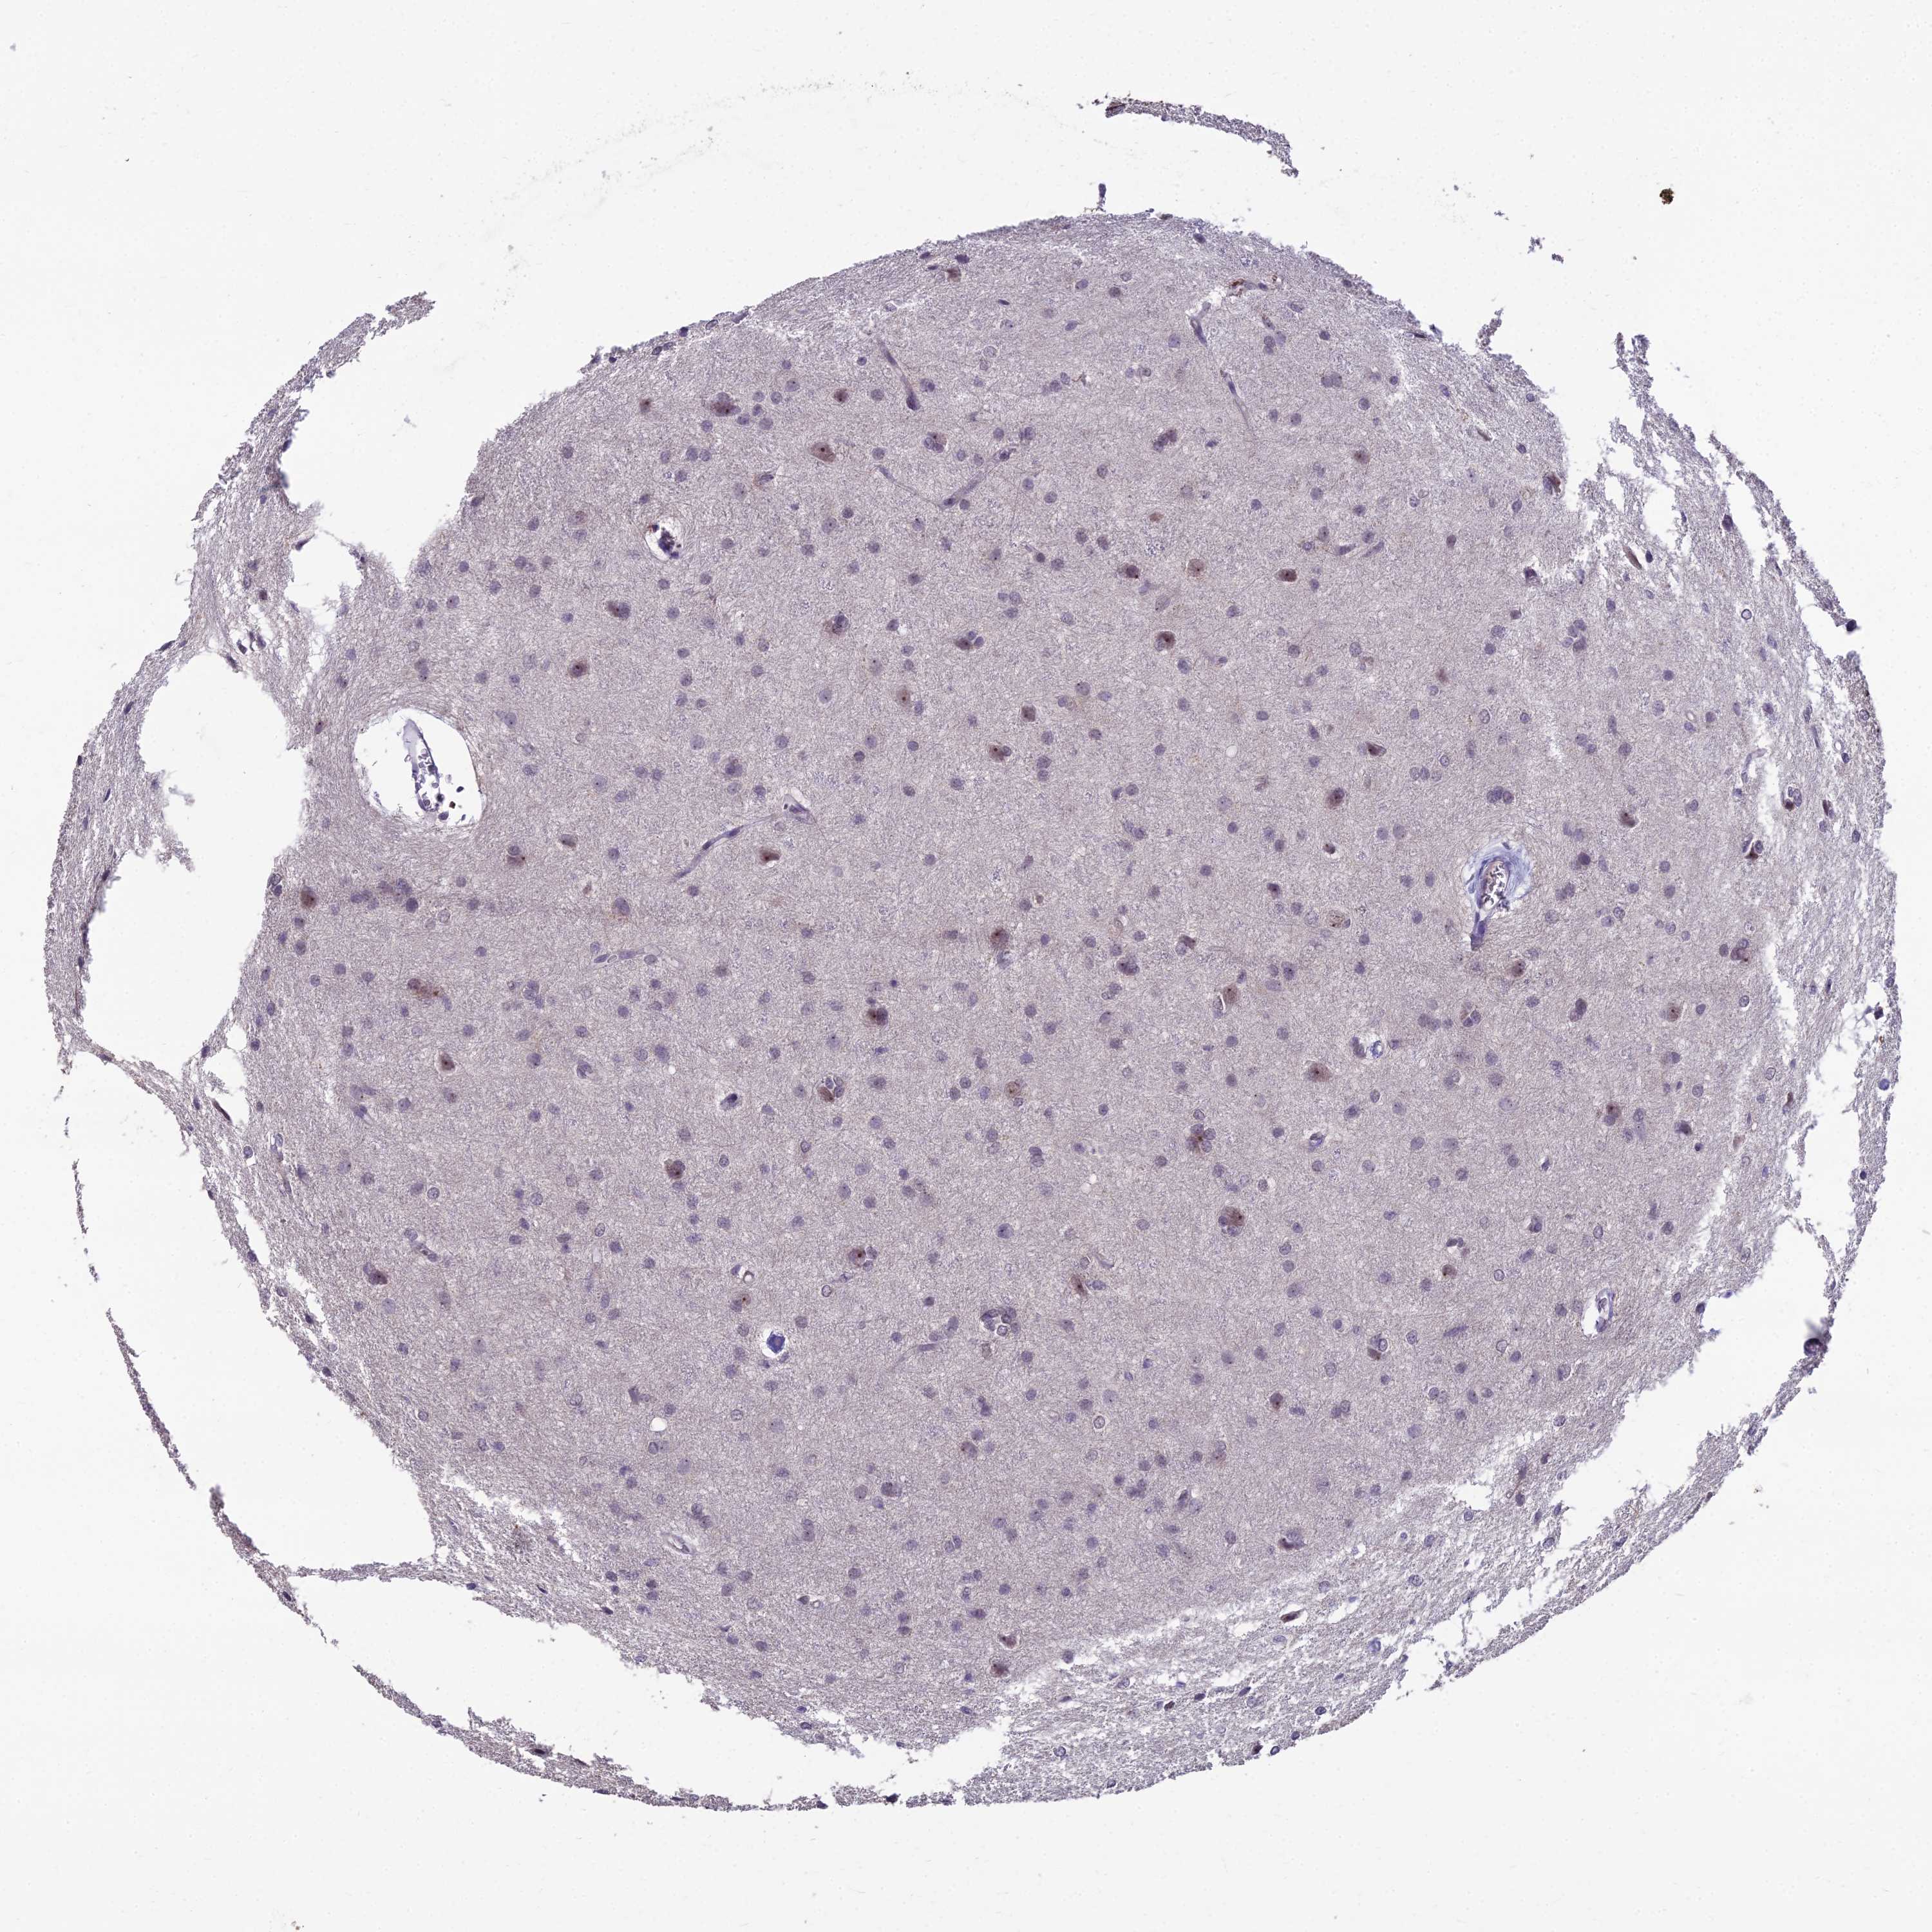

GLIOMA - Protein expressioni

A mouse-over function shows sample information and annotation data. Click on an image to view it in a full screen mode. Samples can be filtered based on level of antibody staining by selecting one or several of the following categories: high, medium, low and not detected. The assay and annotation is described here.

Note that samples used for immunohistochemistry by the Human Protein Atlas do not correspond to samples in the TCGA dataset.

Antibody stainingi

Antibody staining in the annotated cell types in the current human tissue is reported as not detected, low, medium, or high, based on conventional immunohistochemistry profiling in selected tissues. This score is based on the combination of the staining intensity and fraction of stained cells.

Each image is clickable and will lead to virtual microscopy that enables deeper exploration of all samples and also displays staining intensity scores, fraction scores and subcellular localization as well as patient and tissue information for each sample.

Antibody HPA043973

Staining

High

Medium

Low

Not detected

Intensity

Strong

Moderate

Weak

Negative

Quantity

>75%

75%-25%

<25%

None

Location

Nuclear

Cytoplasmic/membranous

Cytoplasmic/membranous,nuclear

Glioma, malignant, High grade

Glioma, malignant, Low grade